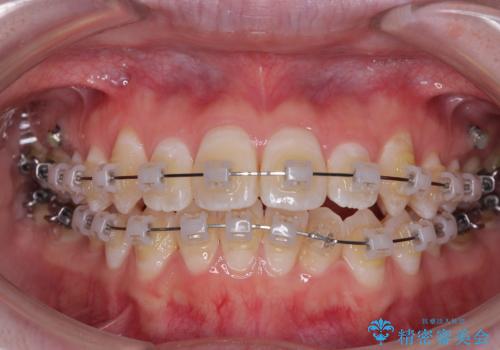

【モニター】前歯のデコボコをスッキリ解消!目立ちにくいワイヤー矯正でスピーディに治療完了

- クリアブラケット

- 「前歯のデコボコ(叢生)をきれいに整えたい」とのことでご来院されました。

マウスピース矯正も検討されていましたが、「装着時間の自己管理が難しそう」「なるべく早く治療を終えたい」とのご希望から、ワイヤー矯正を選択されました。

目立ちにくさと費用のバランスを考慮し、プラスチックブラケット+メタルワイヤーを採用。日常生活でも装置の存在感を気にせずお過ごしいただけます。

患者様の協力もあり、およそ1年間で治療を完了。スムーズな歯の移動を実現しました。

上下の正中(真ん中のライン)もずれることなく、バランスの取れた美しい歯並びに。笑顔に自信を持てる仕上がりとなりました。

「もっと時間がかかると思っていましたが、あっという間でした。装置も思ったより気にならず、前歯がきれいに並んでとても満足しています。」とうれしいお言葉をいただきました。